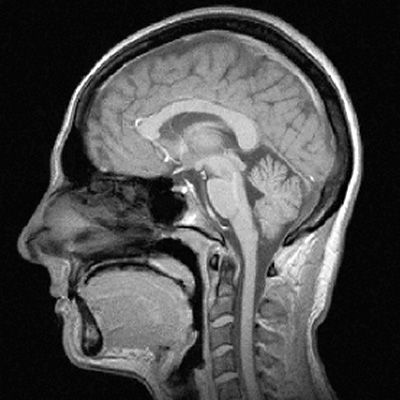

Resonancia Magnética

PREMIUM

Resonancia 1.5T

Philips Prodiva 1.5T. Imágenes de alta definición para diagnósticos neurológicos, articulares y abdominales con precisión milimétrica.

• Campo magnético 1.5 Tesla

• Estudios con y sin contraste

• Interpretación radiológica incluida

Philips Prodiva 1.5T:

Precisión Magnética

Contamos con el sistema de resonancia magnética Philips Prodiva 1.5T, reconocido mundialmente por su calidad de imagen superior, reducción de tiempos de estudio y máximo confort para el paciente.

Neuroimagen Avanzada

Detección temprana de patologías cerebrales con resolución milimétrica.

Tiempos Reducidos

Tecnología Compressed SENSE que reduce hasta un 50% el tiempo de examen.

Seguridad Total

Sistema con detección de cuerpos extraños y monitoreo continuo del paciente.

Philips Prodiva 1.5T

1.5T

Campo Magnético

70cm

Abertura Amplia

4K

Resolución Imagen